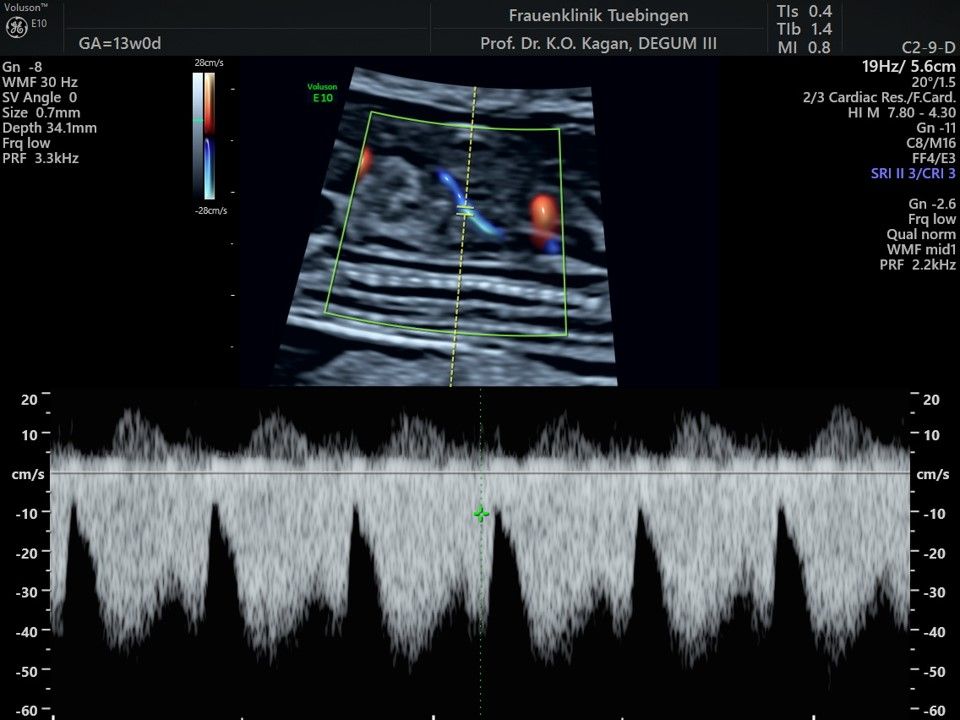

Mithilfe des Ersttrimester-Screenings kann das persönliche Risiko einer Präeklampsie bestimmt werden. Dazu wird die Vorgeschichte der Schwangeren, der aktuelle Blutdruck, das Ergebnis der Ultraschalluntersuchung (Widerstand in den Gebärmutter-nahen Gefäßen) und der Blutabnahme bei Ihnen (PAPP-A) kombiniert. Sollte das Risiko über 1:100 sein, empfehlen wir die tägliche Einnahme von Aspirin 150mg bis zu 35.SSW und eine gezielte Überwachung der weiteren Schwangerschaft.

Das Ergebnis der Ultraschalluntersuchung ist wegweisend. Dabei wird der Fet vermessen, die Organe werden untersucht und die sonographischen Marker zur Risikoberechnung für Chromosomenstörungen werden beurteilt. Das sind: die Nackentransparenzdicke, Nasenbein sowie der Blutfluss in der rechten Herzhälfte und im Ductus venosus, einem Gefäß in der Leber des Feten.